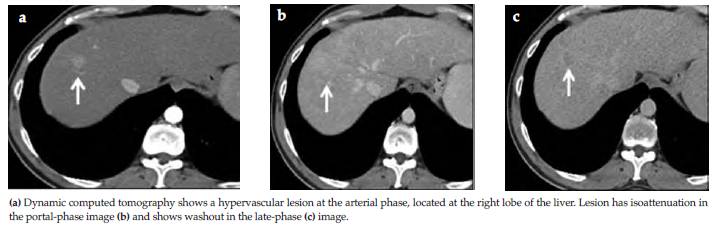

Multiphasic CT and MRI using extracellular agents permit the diagnosis and staging of HCC based mainly on assessing vascularity. The principles are essentially the same for CT and MRI. Using extracellular agents, the hallmark diagnostic features of HCC on multiphasic CT or MRI are arterial-phase hyperenhancement followed by portal venous or delayed-phase washout appearance (Figures 4 and 5). Washout appearance is defined as a visually assessed temporal reduction in enhancement relative to surrounding liver from an earlier to a later phase, resulting in portal venous or delayed-phase hypoenhancement. The pathophysiologic basis for arterial-phase hyperenhancement in HCC is well understood. Intranodular arterial supply increases during hepatocarcinogenesis. Hence, most cirrhotic nodules, dysplastic nodules, and early HCCs are hypoenhancing or isoenhancing during the arterial phase.2

Although the individual features are nonspecific, the combination of arterial-phase hyperenhancement and portal venous and/or delayed-phase washout appearance is highly specific for HCC in patients with cirrhosis. In such patients, this temporal enhancement pattern has approximately 100% specificity for HCCs ≥ 20 mm and ~90% specificity for HCCs of 10 to 19 mm.2

Figure 4. Typical Small Hepatocellular Carcinoma in the Cirrhotic Liver